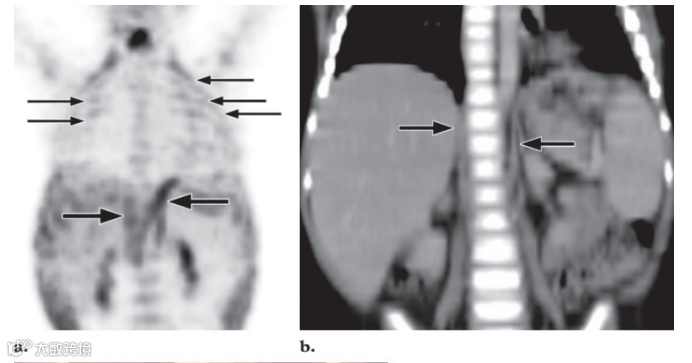

图16. 粒细胞集落刺激因子 (G-CSF) 对一名15岁霍奇金病女孩的效果。两轮化疗后进行FDG PET/CT 检查。

MIP FDG PET 图像显示弥漫性骨骼和脾脏摄取,这一发现反映了粒细胞集落刺激因子 (G-CSF) 诱导的造血作用。

脾脏是免疫系统的重要组成部分,并且具有多种功能,包括清除荚膜细菌、吞噬作用以及产生炎症物质和免疫球蛋白抗体。据推测,脾脏活动的广泛增强反映了脾外感染时该器官的葡萄糖消耗增加。外部放射治疗几个月后,可以观察到骨髓FDG摄取减少。这种现象归因于脂肪组织取代骨髓。通常,正常骨骼中不会发现FDG摄取。然而,骨骼未成熟的儿科患者可能在骨骺和骨突中出现生理线性摄取(图17)。